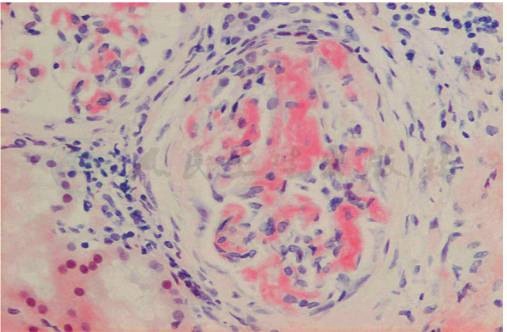

为进一步明确病理诊断,患者行肾活检,病理显示:免疫荧光:IgM(++)、C3(+)、λ(++)、κ(-);系膜区颗粒样沉积,其余免疫球蛋白均为阴性;光镜:17个肾小球,肾小球系膜区、节段性毛细血管壁可见无细胞结构性特殊蛋白沉积,刚果红染色阳性。小动脉管壁增厚伴淀粉样蛋白沉积(图1),偏振光显示为双折光苹果绿色(图2)符合淀粉样变性肾病。电镜:肾小球系膜区及节段性基底膜无细胞性不规则增宽,可见直径8~10nm的淀粉样纤维沉积,上皮足突弥漫融合,未见电子致密物(图3),符合淀粉样变性肾病。该病理结果证实患者为淀粉样变性病的诊断。患者病理λ轻链染色阳性,结合患者血清单克隆免疫球蛋白轻链λ阳性,考虑患者为轻链型(AL型)淀粉样变性病。

图1 AL型淀粉样变性病:肾小球系膜区大块刚果红染色阳性的特殊蛋白沉积(刚果红染色×400)